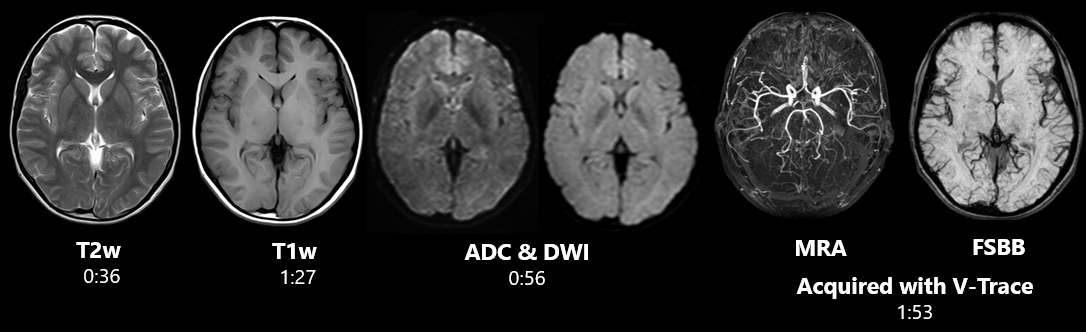

Обстеження головного мозку за короткий час доступне з Vantage Elan 1.5T. Завдяки поєднанню базових технологій ATLAS, Pianissimo™, SPEEDER проведення досліджень займають мінімум часу та надають максимум комфорту для пацієнта. Завдяки поєднанню різних анатомічних котушок.